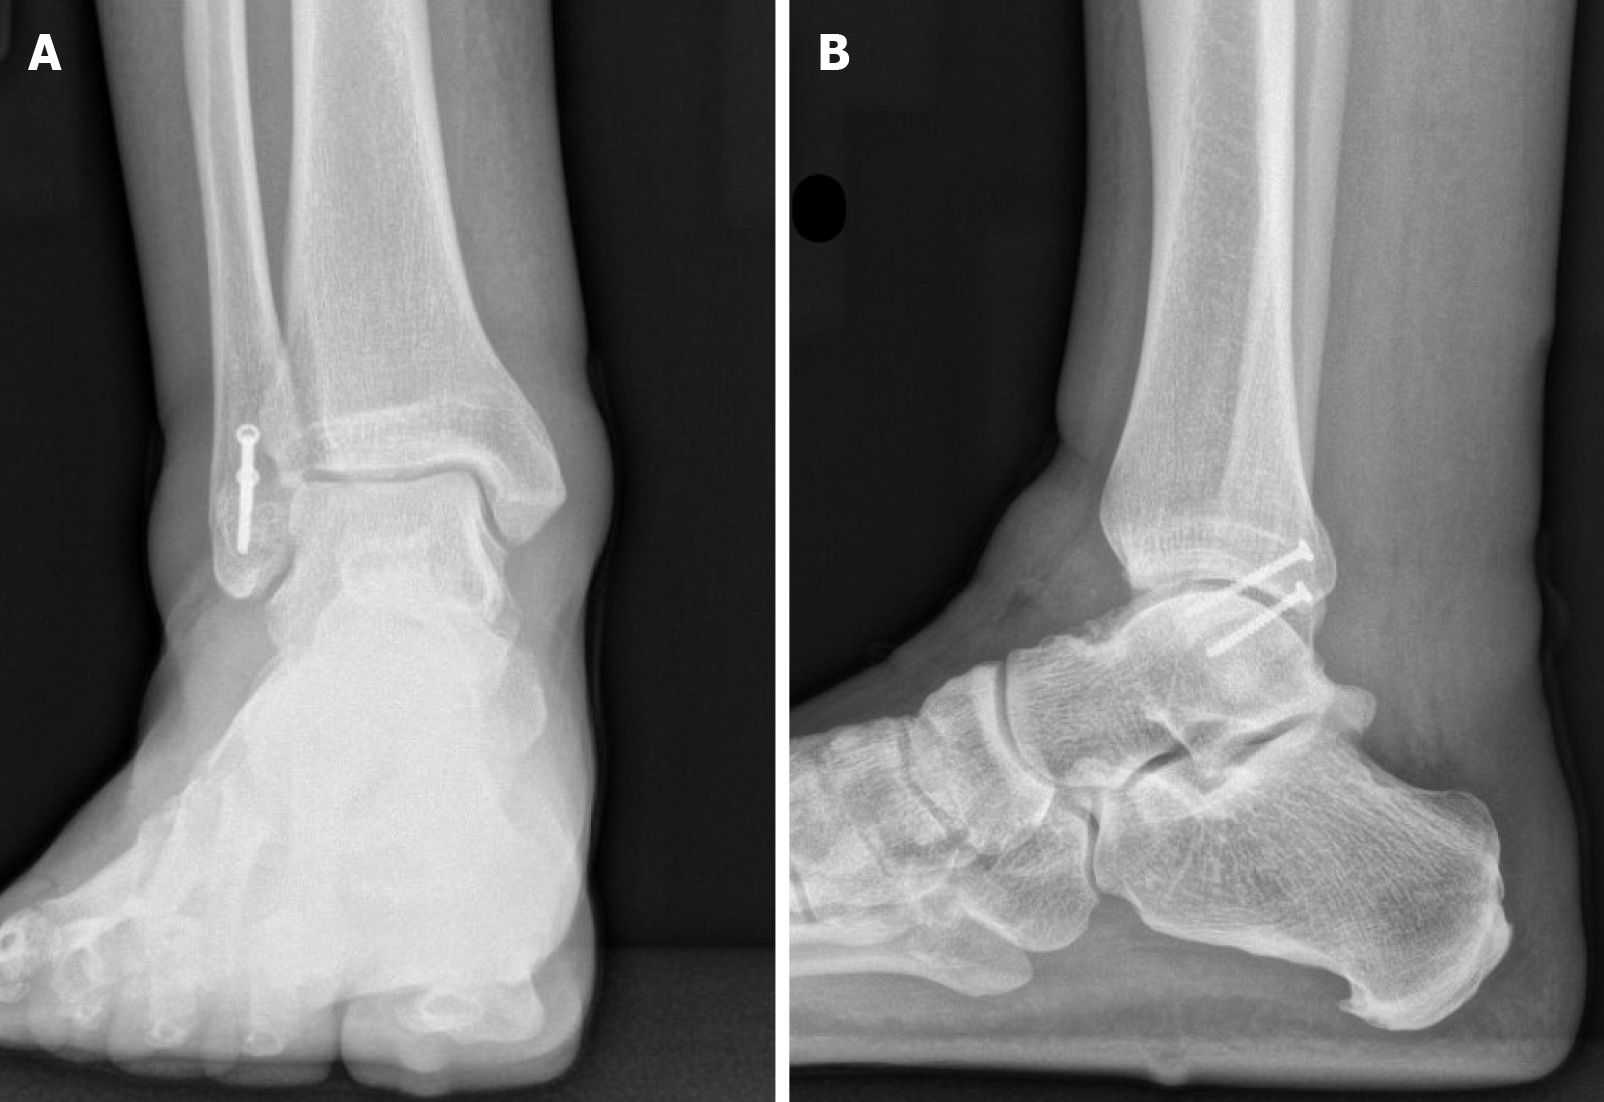

Figure 7 Weight bearing X-rays of the ankle demonstrating well healed distal fibula fracture.

A: Anterior-posterior; B: Lateral view.